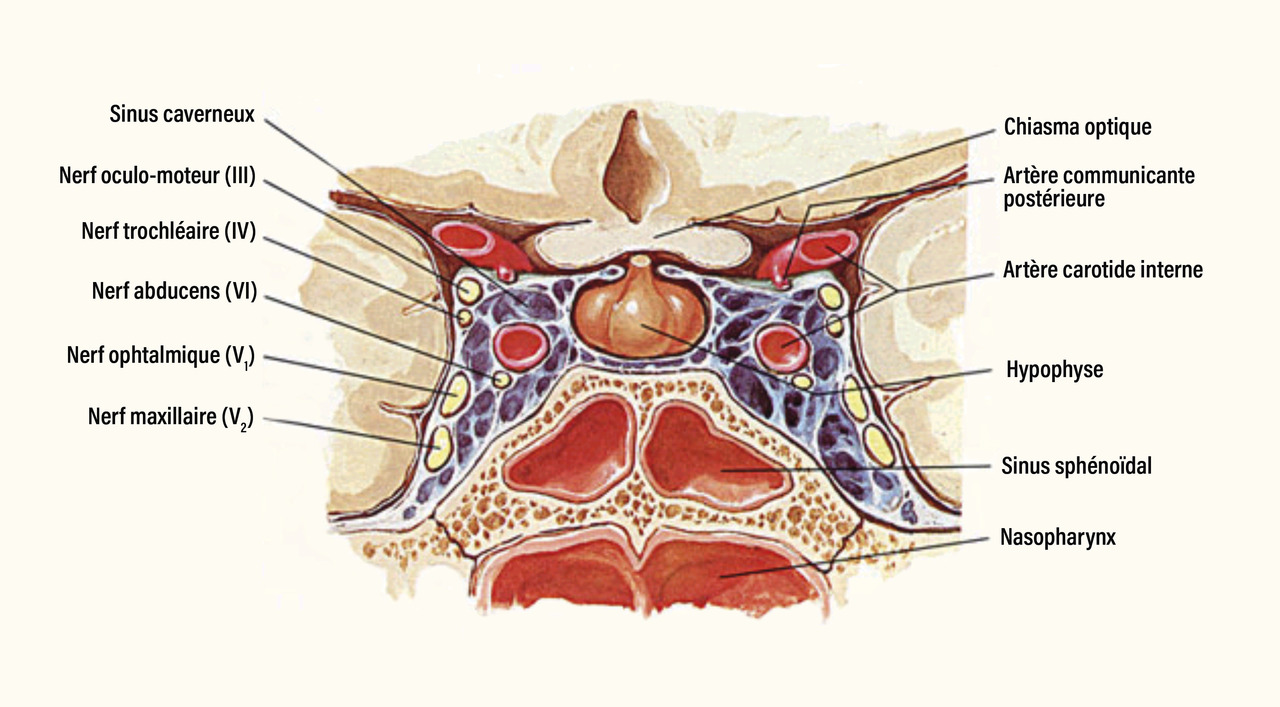

L’hypophyse est une glande située à la base du cerveau, dans une cavité osseuse appelée selle turcique (fig. 1). Cette glande contrôle de nombreux processus vitaux tels que la croissance, la maturation sexuelle, la reproduction, le stress, le métabolisme basal. Elle assure une fonction de relais entre l’hypothalamus et les glandes endocrines périphériques.

Les adénomes peuvent être invasifs en infiltrant les sinus caverneux sur les côtés, ou le plancher sellaire en bas, ou la citerne optochiasmatique, voire le plancher du troisième ventricule en haut.

Les troubles visuels sont liés à une compression du chiasma optique, qui est situé juste au-dessus de l’hypophyse. Les patients peuvent se plaindre d’une sensation de flou visuel, de voile devant les yeux, plus rarement ils remarquent une altération de leur champ de vision (accident de voiture par non-perception d’un autre véhicule arrivant sur le côté).

• une paralysie oculomotrice liée à une compression des nerfs crâniens (III, IV et VI) dans le sinus caverneux (fig. 1) ;